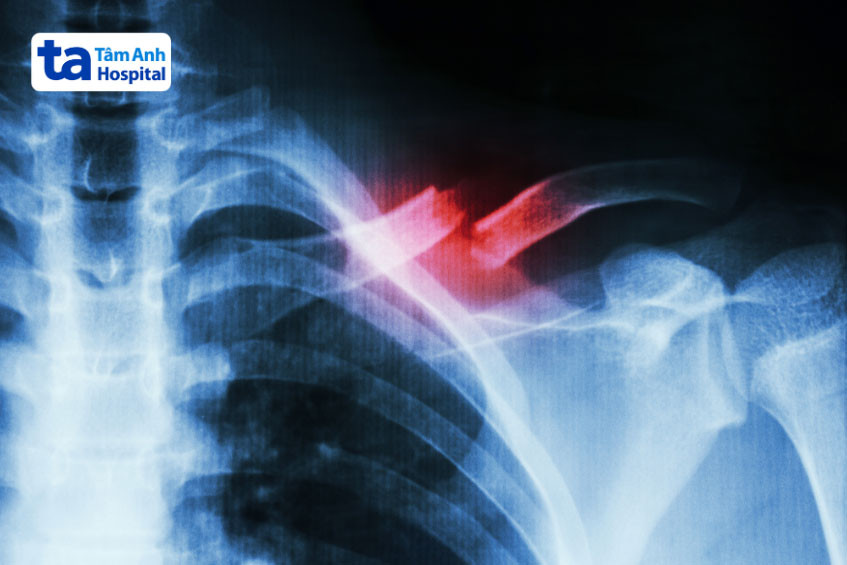

Gãy xương đòn

Xương đòn (còn gọi là xương quai xanh) là xương dài nối xương ức và hệ thống đai vai – cánh tay. Xương này được xem như một thanh chắn, cho phép vai hoạt động tối ưu, đồng thời bảo vệ các cấu trúc quan trọng như phổi, đám rối cánh tay, bó mạch dưới đòn…

Ngã chống tay khiến phần vai va chạm mạnh có thể trực tiếp hoặc gián tiếp gây gãy xương đòn. Ngoài ra, tai nạn giao thông, lao động hoặc chấn thương thể thao cũng có khả năng làm gãy xương quai xanh. Lúc này, vùng vai có thể đau, sưng, bầm tím và hõm xuống khiến người bệnh gặp khó khăn khi cử động vai.

Gãy xương đòn gây đau vai gáy bên trái